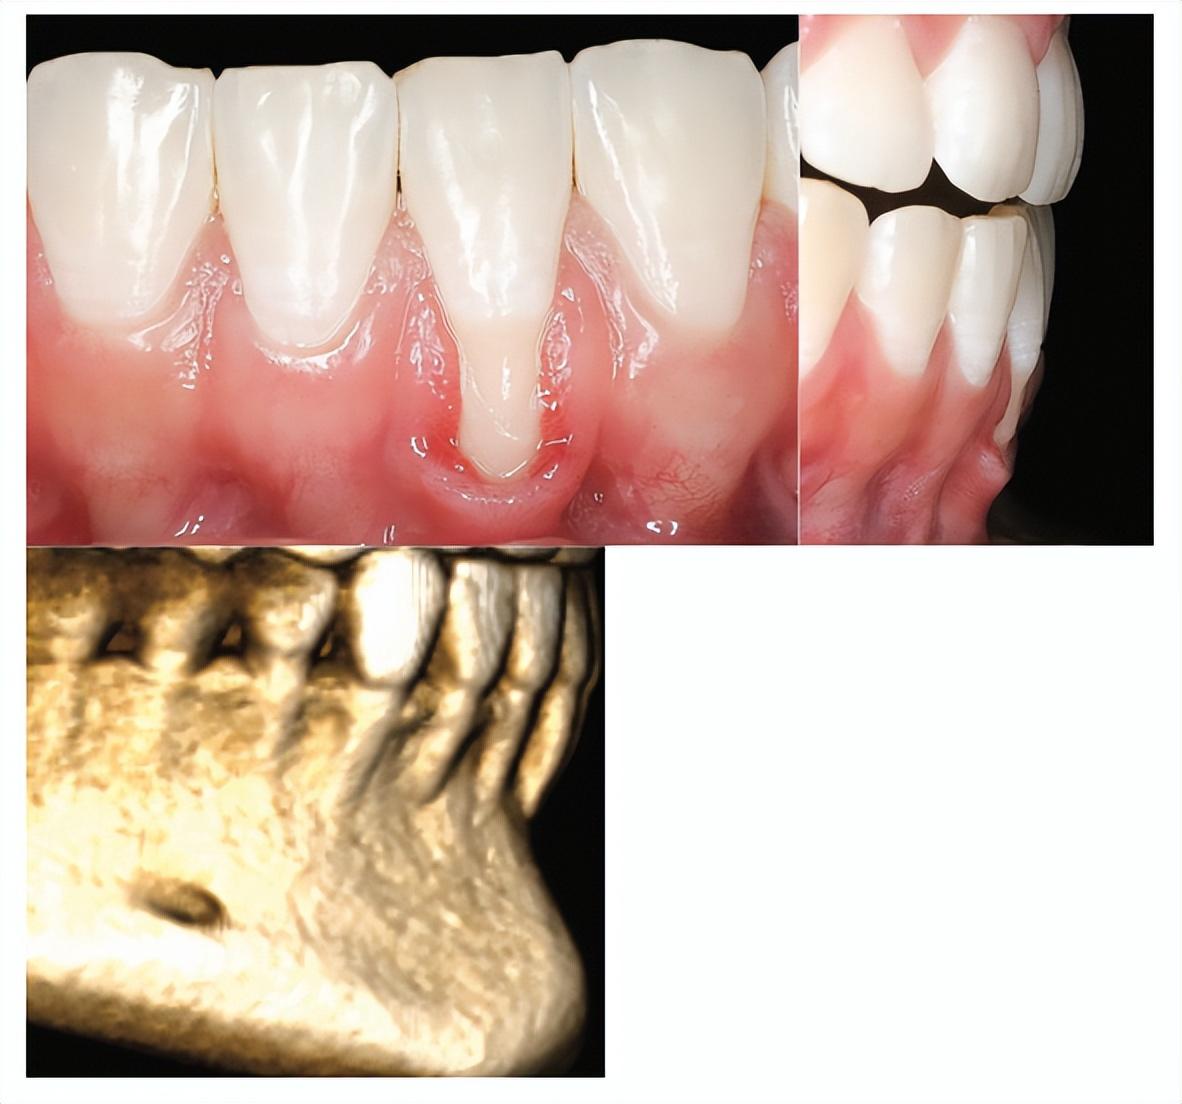

正畸治疗是否会导致牙龈萎缩?这个问题一直备受争议。根据流行病学调查,正畸治疗过程中的牙龈退缩发生率为1.3%~12%。虽然有研究未发现牙齿移动与牙龈退缩之间的直接关联,但也有研究显示正畸治疗是牙龈退缩发生的危险因素之一。

牙龈萎缩是指牙龈边缘向釉牙骨质界的根方移动,导致牙根暴露。在正畸治疗中,牙龈萎缩可能由多种因素引起。首先,牙齿的移动如果突破了牙槽突的生理范围,如过度扩弓或过度的唇、舌倾,可能会导致牙根挤压菲薄的骨板,造成其快速吸收,继而引发牙龈退缩。其次,局部菌斑控制不佳也是导致牙龈萎缩的重要原因。佩戴正畸装置会影响患者的口腔卫生措施及牙齿的自洁功能,增加局部菌斑控制的难度。

牙龈萎缩不仅影响美观,还可能导致一系列口腔健康问题。牙根暴露后,牙齿可能会变得更加敏感,对冷热刺激、化学物质或机械刺激产生不适反应。此外,相邻牙齿之间的牙龈萎缩还可能导致食物嵌塞,进而引发根面龋。对于前牙,牙龈萎缩还可能影响患者的自信心,使其笑时不敢露齿。